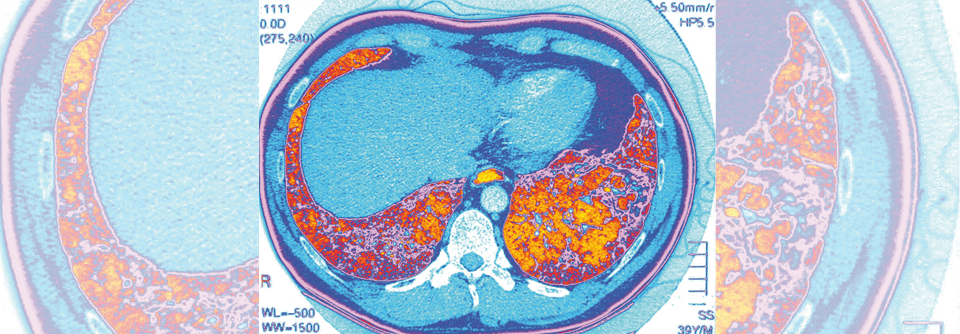

Bei einer Reihe von rheumatischen Erkrankungen ist die Lunge in Form einer interstitiellen Lungenerkrankung (ILD) beteiligt. Am häufigsten kommt dies bei der systemischen Sklerose vor. Dabei ist die ILD eine Komplikation, die sehr früh beginnt: Schon im ersten Erkrankungsjahr machen sich Auswirkungen auf die Lungenfunktion bemerkbar. Langfristig reduziert die Lungenbeteiligung die Zehn-Jahres-Überlebensrate der systemischen Sklerose von 82 % auf 69 %, erläuterte Prof. Dr. Gabriela Riemekasten, Leiterin der Klinik für Rheumatologie an der Universität zu Lübeck.

Häufig liegt Mosaikmuster vor

Histologisch finden sich bei der interstitiellen Lungenerkrankung im interstitiellen Gewebe…